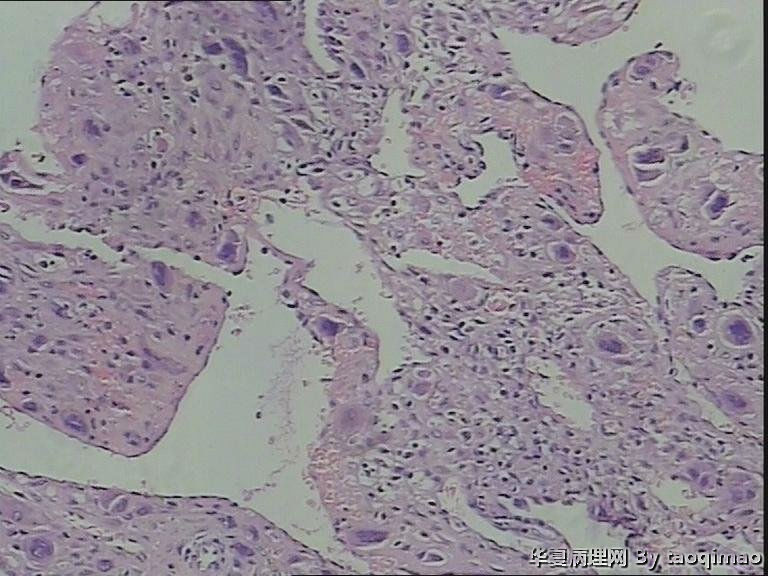

• 功血,滋养细胞浅肌层?图1

图1

这是患者第一次刮宫的内膜,怎么出报告呢

患者资料:39岁女,阴道不规则出血,2011,6,诊刮可见:内膜腺体囊性增生,现再次出血诊刮术。术中子宫后位,宫深9cm,子宫增大内膜不平,刮出内膜组织约2g。红褐色破碎组织一堆大小3X2.5cm,质软。